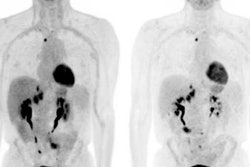

Radiomic factors -- that is, image-based tumor phenotypes -- gleaned from F-18 FDG PET exams can help clinicians personalize care and better predict treatment outcomes for patients with head and neck squamous cell carcinoma (HNSCC), according to a study published on 7 September in EJNMMI Research.

The researchers hypothesized that developing a list of quantitative F-18 FDG PET radiomic features in patients with HNSCC could help predict recurrence, metastasis, and overall survival who had undergone chemotherapy and radiation therapy treatment.

The study included 71 patients who had F-18 FDG PET/CT imaging between 2012 and 2018. From these exams, the researchers extracted 434 radiomic features that they then assessed for their predictive value, tracking correlation with clinical factors (including human papillomavirus infection [HPV] status, which can affect a person's vulnerability to radiation) and PET parameters such as mean standardized uptake values (SUVmean).